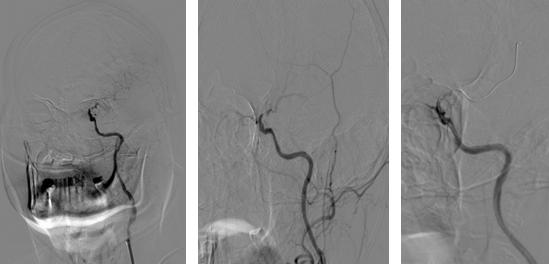

神经内科郝永岗副主任医师与神经血管介入团队充分讨论患者病情,完善术前相关检查及药物准备,排除禁忌症,决定为患者实施经皮左颈内动脉颅内段球囊扩张成形术。9月8日,我院神经血管介入团队在MRI-DSA杂交手术室于局部麻醉下为患者实施手术,历时70分钟,成功扩张成形病变血管,使脑血流明显改善,挽救了处于缺血状态的神经细胞,避免了梗死核心进一步扩大。术后经过神经内科及康复医学科联合积极治疗,胡大爷右侧肢体肌力明显增强。

(术前造影左侧颈内动脉C6段次全闭塞血流缓慢)